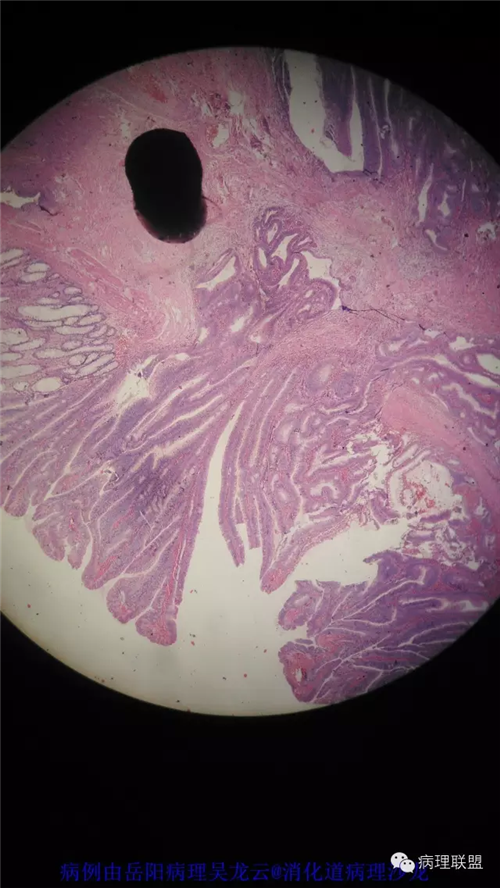

病例2

女性,60岁,结肠腺瘤活检。有一灶腺体突破粘膜肌,腺体无明显异形。

(注:病例由岳阳病理吴龙云提供 致谢!)